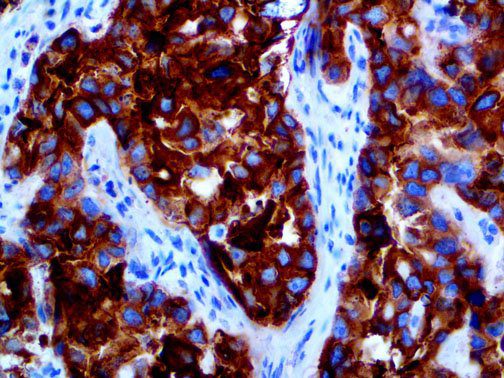

It is the ICU physician who is most likely to witness one of the deadliest manifestations of the abnormal immunological response, the cytokine storm syndrome (CSS). This response is also referred to by some as the cytokine release syndrome (CRS). CSS is characterized by continuous activation and expansion of macrophage and lymphocyte populations, which secrete large amounts of cytokines, causing the cytokine storm. This massive cytokine release is akin to hemophagocytic lymphohistiocytosis (HLH) disease, a syndrome characterized by initial unchecked and persistent activation of cytotoxic T lymphocytes and NK cells.

Clinical and laboratory manifestations of HLH include fever, enlarged liver and/or spleen, neurologic dysfunction, coagulopathy, liver dysfunction, cytopenias (i.e., low levels of erythrocytes, leukocytes, and/or platelets), hypertriglyceridemia, hyperferritinemia, hemophagocytosis, and eventually diminished NK cell activity as the immune system becomes progressively paralyzed. HLH can be familial (primary HLH) or secondary to another disease process (sHLH), such as rheumatic disease, in which it is referred to as macrophage activation syndrome (MAS, characterized by elevated ferritin).

This activation induces inflammatory monocytes to highly express IL-6, starting a localized and then systemic cascade effect that results in hyperproduction of IL-6, which accelerates the inflammatory process. Because IL-6 also increases vascular permeability, excessive levels cause blood vessels to become very leaky. This, along with clotting factors released from vascular endothelial cells, stimulates the coagulation cascade, resulting in microthrombosis (tiny clots), which leads to ischemia and tissue death of the kidney, intestines, heart, liver, brain and extremities.